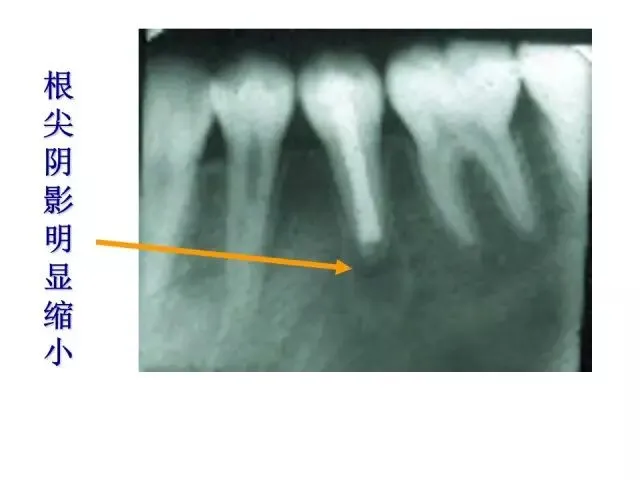

>PPT典藏 | 根尖诱导成型术

PPT典藏 | 根尖诱导成型术